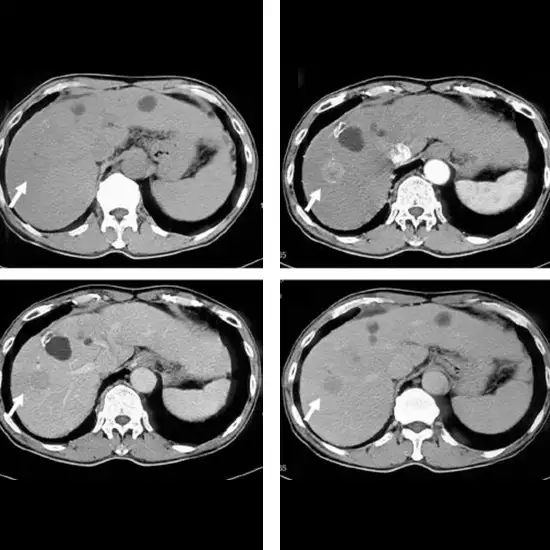

Triple Phase CT Abdomen is an imaging scan that provides detailed images of the abdominal structure. In this scan, an X-ray beam is used to generate detailed pictures of the organs such as the GI Tract, Liver, Kidney, Pancreas, Spleen, etc. that are inside the abdomen. This scan is recommended by a doctor to diagnose the root cause of problems if the patient has symptoms such as blood in urine, abdominal pain, abdominal swelling, hernia, or kidney stone. It is also used to diagnose/detect cancers such as the renal pelvis, hepatocellular, lymphoma, melanoma, ovaries, pancreas, and Pheochromocytoma.